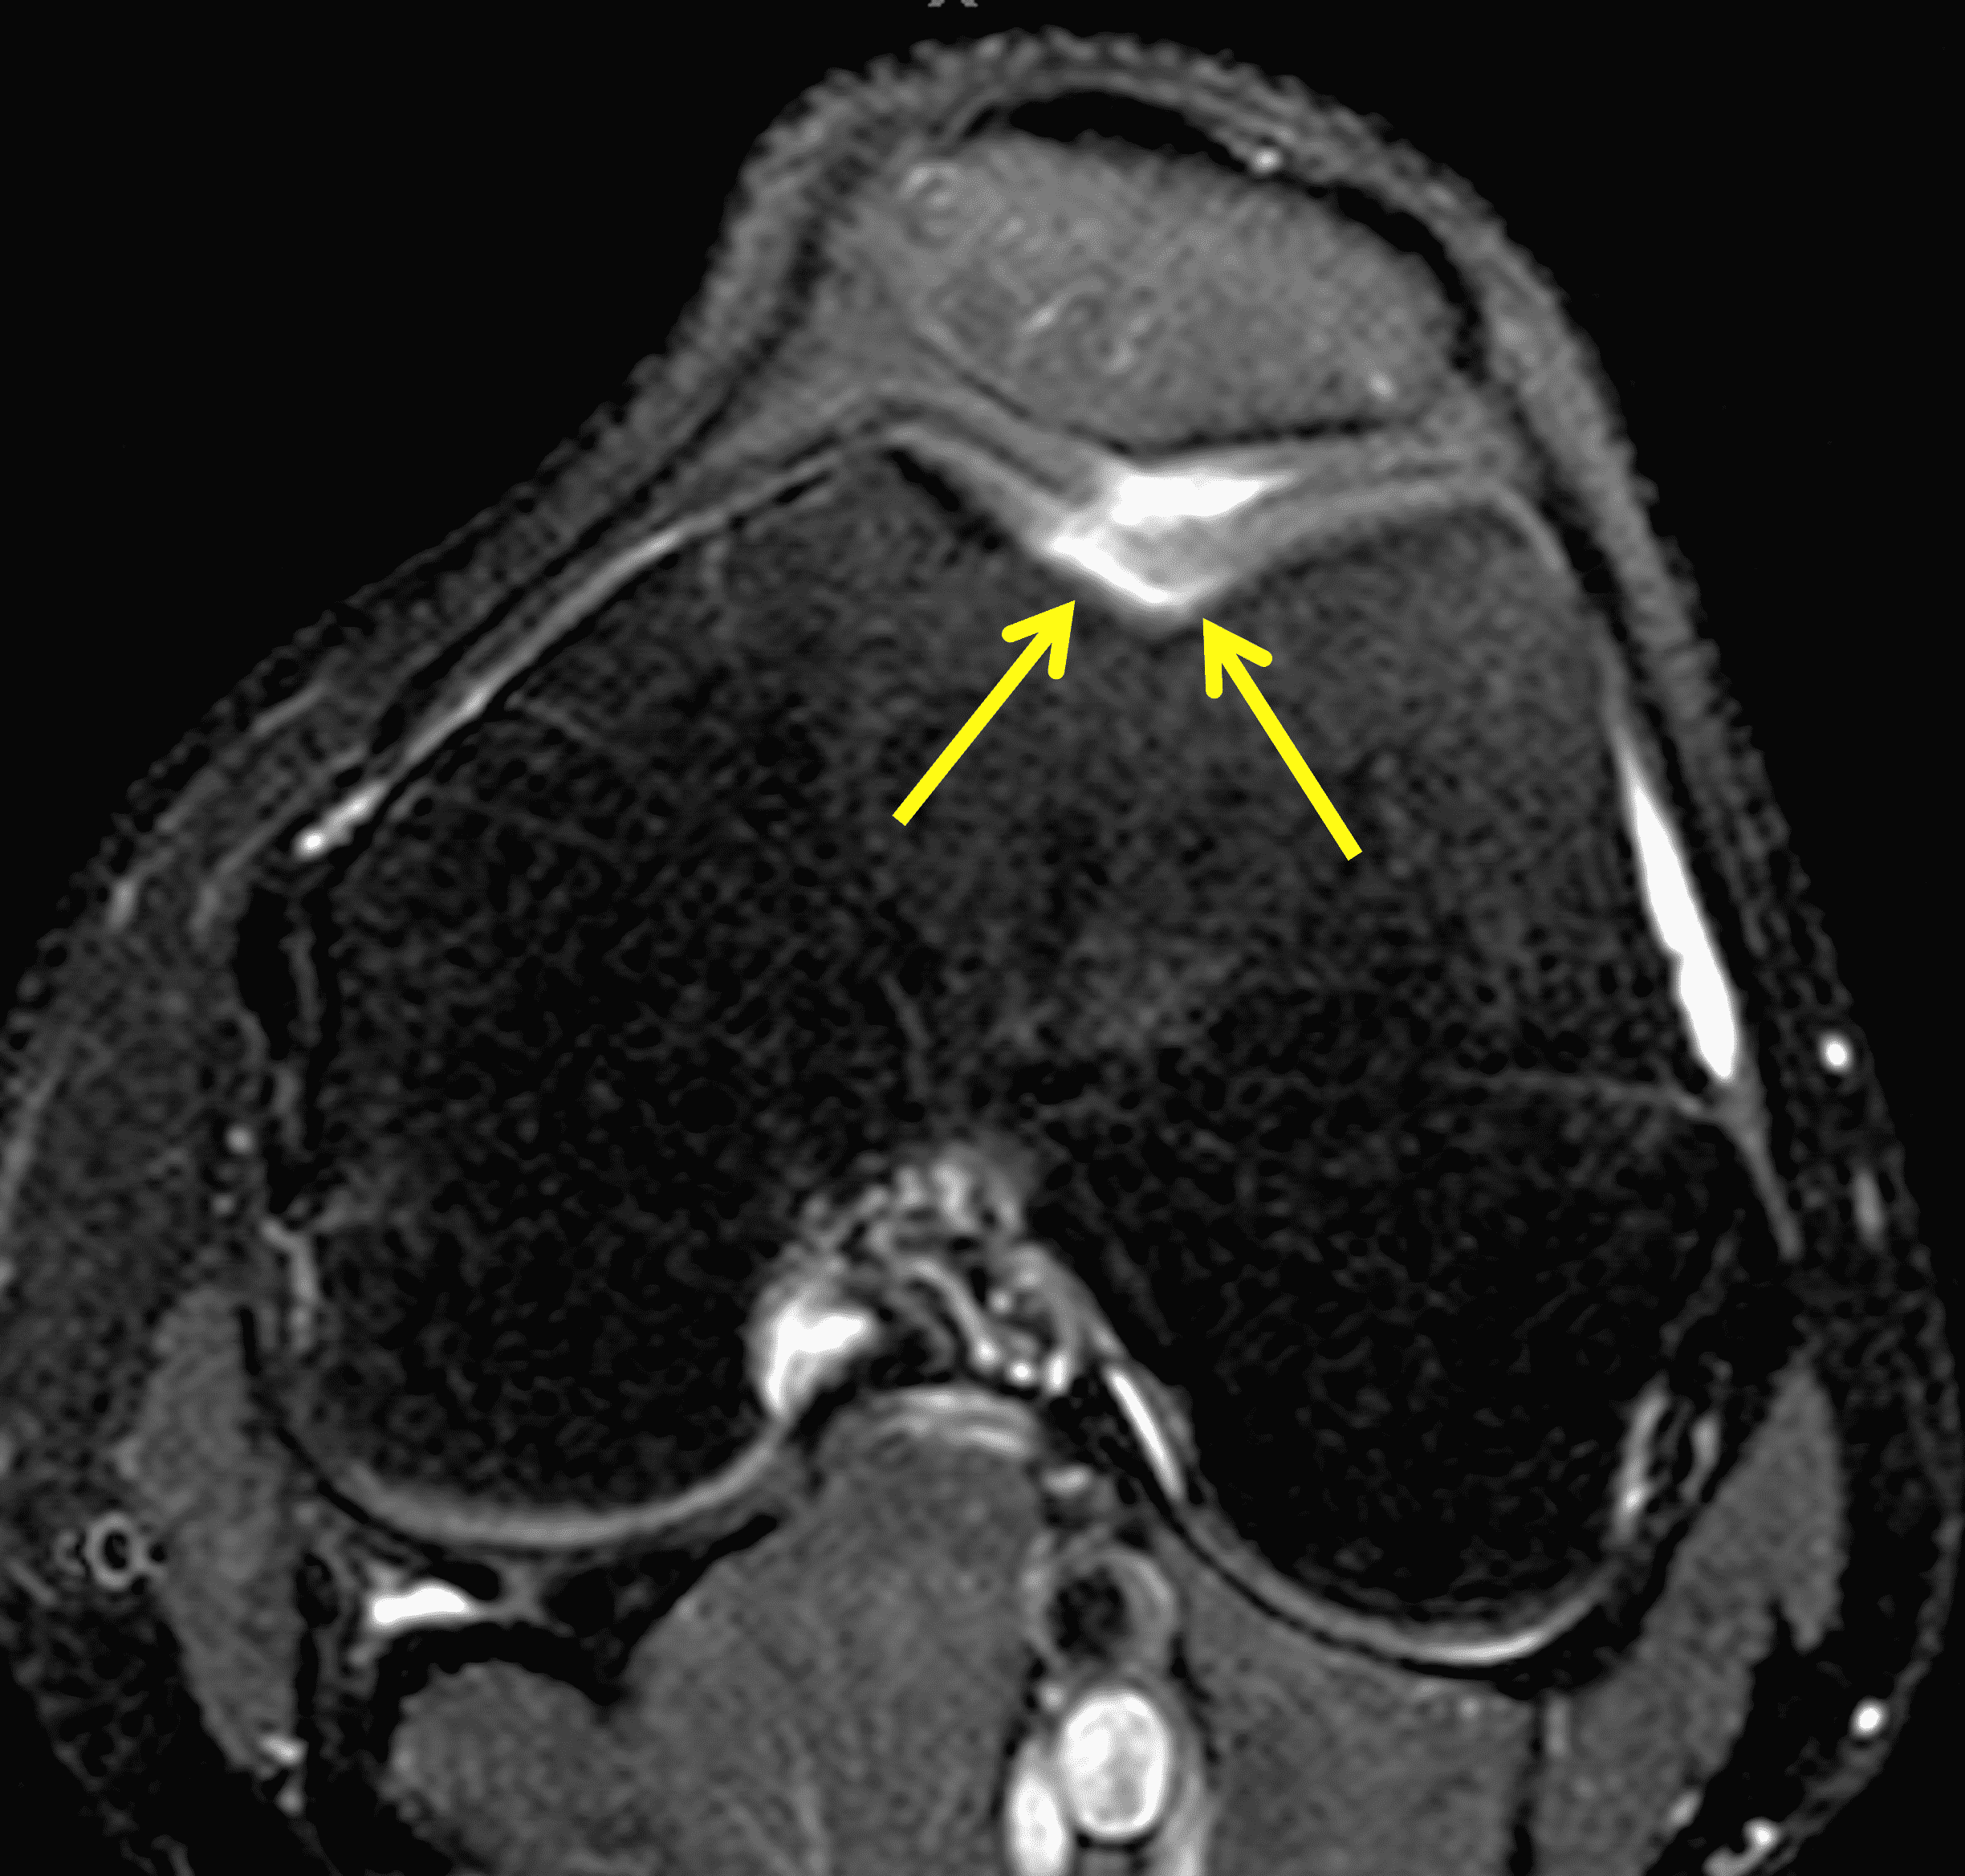

A 32-year-old man suffered a traumatic chondral injury to the medial femoral condyle that was treated with an osteochondral allograft 20 months previously. Representative images from a current knee MRI include (1A) coronal fat-suppressed fluid-sensitive and sagittal (1B) T1-weighted, (1C) proton density-weighted, and (1D) T2-weighted sequences. Are the post-operative MRI findings normal and expected, or abnormal and pathologic? Based on these images, would you characterize the procedure as a success or failure?

Figure 2: (2A) On the coronal image, the margins of the osteochondral graft are faintly visible (arrowheads). Both the graft and underlying bone show mild marrow edema, an expected finding. (2B) The T1-weighted image shows continuity of the marrow in the graft (asterisks) with the underlying bone, indicating osseous integration. A bioabsorbable pin (arrow) used for graft fixation is partly visible. (2C) The proton density-weighted image shows a low signal intensity seam (black arrow) between the native cartilage and transplant, as well as a defect in the subchondral bone plate of the graft (red arrow) where the pin was drilled, both normal findings. (2D) The T2-weighted image shows a smooth, congruent articular surface (arrows), restoring the normal anatomy, and a tiny subchondral cyst. No findings are present to suggest graft failure. The patient’s current symptoms were attributed to pathology elsewhere in the joint (not shown).

Successful osteochondral allograft procedure.

The postoperative imaging appearance of osteochondral allografts is similar to autografts (Figure 2).33 The subchondral bone plate of the donor and recipient sites do not have to match, but the articular surface should be congruent. Grafts that fail to incorporate by one year have a poor prognosis. Persistent marrow edema (beyond 12 months), a thick graft interface containing cysts or fluid, and subsidence of the graft are associated with poor osseous healing and worse outcomes. Extensive host marrow edema and severe synovitis may be a clue to immunologic rejection of the graft (Figure 18).21, 34